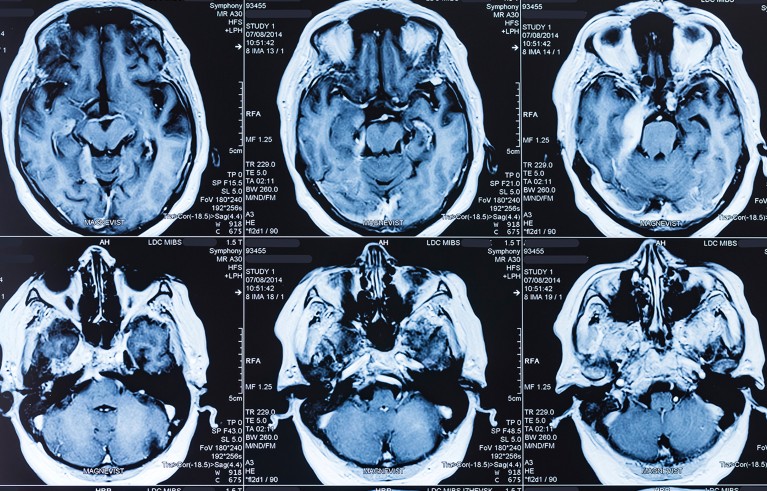

From MRI to Ozempic: breakthroughs that show why fundamental research must be protected